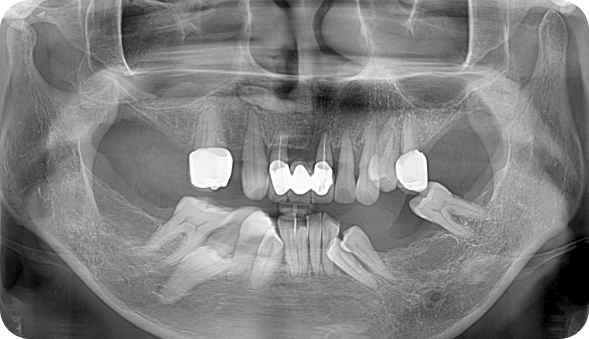

CASE A

환자명 : 김OO 2025.05.20 업데이트

수술 전 촬영일자 : 2023.10.06

수술 후 촬영일자 : 2024.04.23

수술 전(Before)수술 후(After)